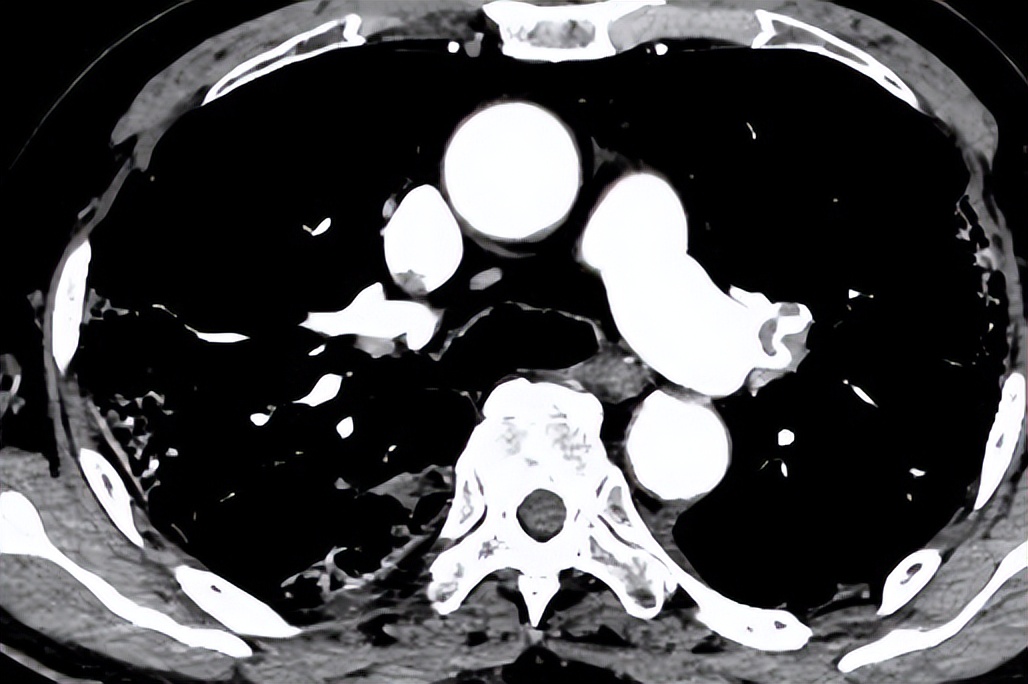

我嘱咐急诊的主管医生要小心有没有血栓的问题,CTPA提示双肺多发斑片渗出影,双肺动脉及分支多发充盈缺损,双侧胸腔积液。但双下肢静脉超声未见血栓。

这位患者为什么会出现血栓?新冠感染已经一个月了,症状已经没有了,但仍然出现了血栓相关症状。

我们将患者从急诊收到普通病房后,管床医生特别慎重,因为患者年龄非常大,已经95岁了,如何用抗凝药物?抗凝为低分子量肝素 0.3ml q12h 皮下注射,但在监测肾功能时发现异常,于是低分子量肝素由0.3q12h减量至0.3qd。